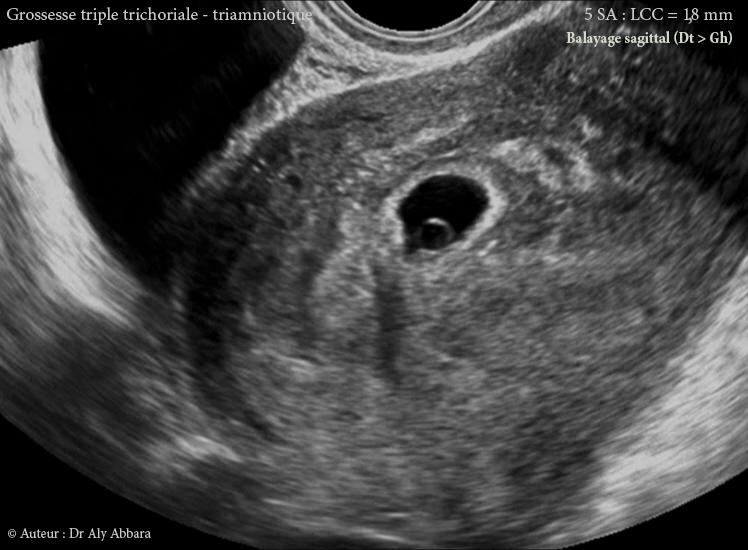

Grossesse multiple triple évolutive trichoriale triamniotique de 5 SA